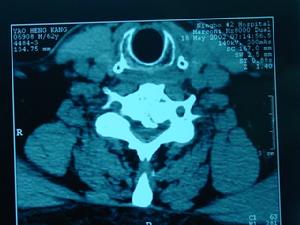

頸椎病又稱頸椎綜合徵,是頸椎骨關節炎、增生性頸椎炎、頸神經根綜合徵、頸椎間盤脫出症的總稱,是一種以退行性病理改變為基礎的疾患。主要由於頸椎長期勞損、骨質增生,或椎間盤脫出、韌帶增厚,致使頸椎脊髓、神經根或椎動脈受壓,出現一系列功能障礙的臨床綜合徵。表現為頸椎間盤退變本身及其繼發性的一系列病理改變,如椎節失穩、鬆動;髓核突出或脫出;骨刺形成;韌帶肥厚和繼發的椎管狹窄等,刺激或壓迫了鄰近的神經根、脊髓、椎動脈及頸部交感神經等組織,並引起各種各樣症狀和體徵的綜合徵。

頸椎病頸椎病發病機理:1、頸椎退行性改變:隨著年齡的不同階段發展,頸椎及椎間盤可發生不同的改變,在頸椎體發生退行性改變的同時,椎間盤也發生相應改變。2、外傷因素:在椎間盤退變的基礎上,進行劇烈活動或不協調的運動。3、慢性勞損:長期處於不良的勞動姿勢,椎間盤受到來自各種方面的牽拉、擠壓或扭轉。4、寒冷、潮濕:尤其在椎間盤退變的基礎上,受到寒冷、潮濕因素的影響,可造成局部肌肉的張力增加,肌肉痙攣,增加對椎間盤的壓力,引起纖維環損害。

頸椎病的基本病理變化是椎間盤的退行性變。頸椎位於頭顱與胸廓之間,頸椎間盤在承重的情況下要做頻繁的活動,容易受到過多的細微創傷和勞損而發病。其主要病理改變是:早期為頸椎間盤變性,髓核的含水量減少和纖維環的纖維腫脹、變粗,繼而發生玻璃樣變性,甚至破裂。頸椎間盤變性後,耐壓性能及耐牽拉性能減低。當受到頭顱的重力和頭胸間肌肉牽拉力的作用時,變性的椎間盤可以發生局限性或廣泛性向四周隆突,使椎間盤間隙變窄、關節突重疊、錯位,以及椎間孔的縱徑變小。由於椎間盤的耐牽拉力變弱,當頸椎活動時,相鄰椎骨之間的穩定性減小而出現椎骨間不穩,椎體間的活動度加大和使椎體有輕度滑脫,繼而出現後方小關節、鉤椎關節和椎板的骨質增生,黃韌帶和項韌帶變性,軟骨化和骨化等改變。由於頸椎間盤向四周膨隆,可將其周圍組織(如前、後縱韌帶)及椎體骨膜掀起,而在椎體與突出的椎間盤及被掀起的韌帶組織之間形成間隙,稱"韌帶間盤間隙",其中有組織液積聚,再加上微細損傷所形起的出血,使這種血性液體發生機化然後鈣化、骨化,於是形成了骨贅。椎體前後韌帶的鬆弛,又使頸椎不穩定,更增加了受創傷的機會,使骨贅逐漸增大。骨贅連同膨出的纖維環,後縱韌帶和由於創傷反應所引起的水腫或纖維疤痕組織,在相當於椎間盤部位形成一個突向椎管內的混合物,就可能對脊神經或脊髓產生壓迫作用。鉤椎關節的骨贅可從前向後突入椎間孔壓迫神經根及椎動脈。椎體前緣的骨贅一般不會引起症狀,但文獻上也有這種前骨贅影響吞咽或造成嘶啞的報告。脊髓及神經根受壓後,開始時僅為功能上的改變,如不及時減輕壓力,逐漸會產生不可逆的變化。因此如果非手術治療無效,應及時進行手術治療。